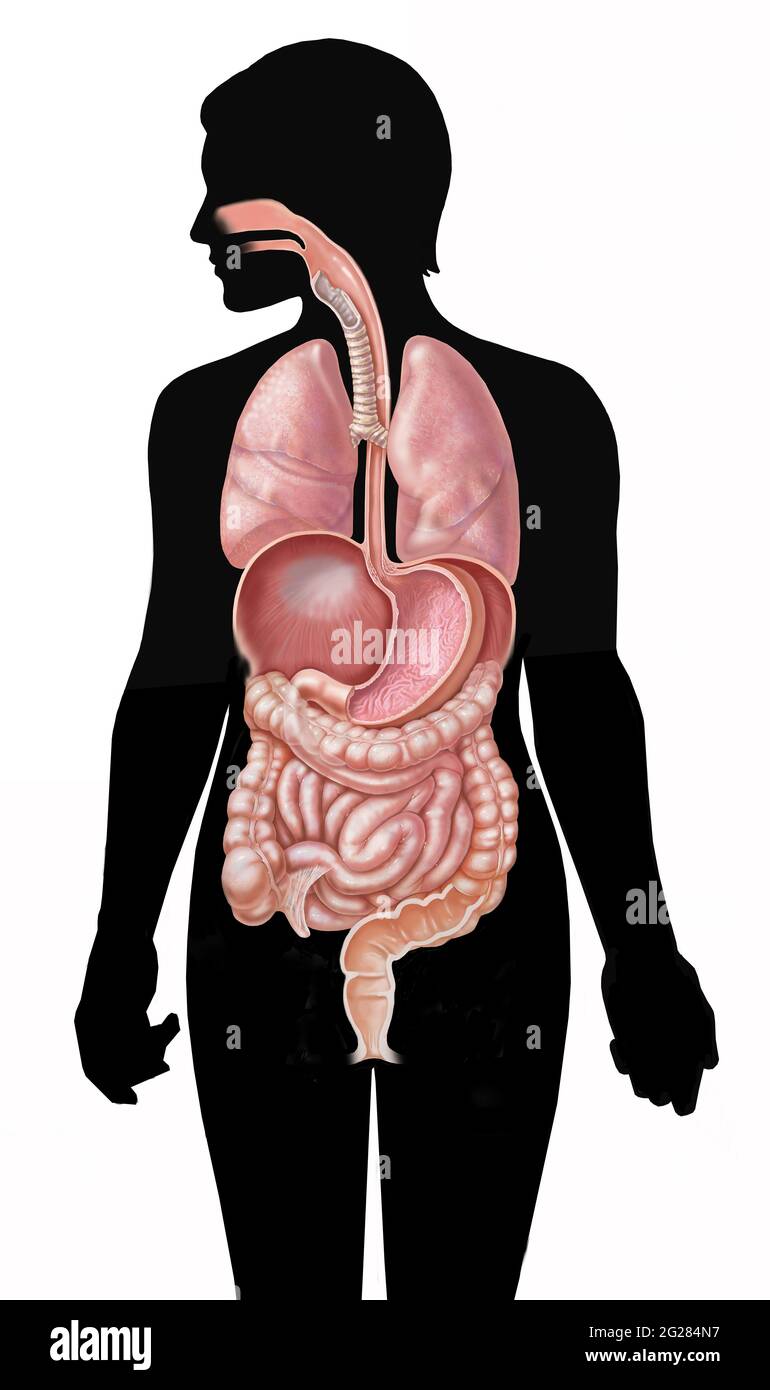

Système gastro-intestinal complet et poumons et diaphragme sur silhouette féminine. Banque D'Imageshttps://www.alamyimages.fr/image-license-details/?v=1https://www.alamyimages.fr/systeme-gastro-intestinal-complet-et-poumons-et-diaphragme-sur-silhouette-feminine-image431667859.html

Système gastro-intestinal complet et poumons et diaphragme sur silhouette féminine. Banque D'Imageshttps://www.alamyimages.fr/image-license-details/?v=1https://www.alamyimages.fr/systeme-gastro-intestinal-complet-et-poumons-et-diaphragme-sur-silhouette-feminine-image431667859.htmlRM2G284N7–Système gastro-intestinal complet et poumons et diaphragme sur silhouette féminine.